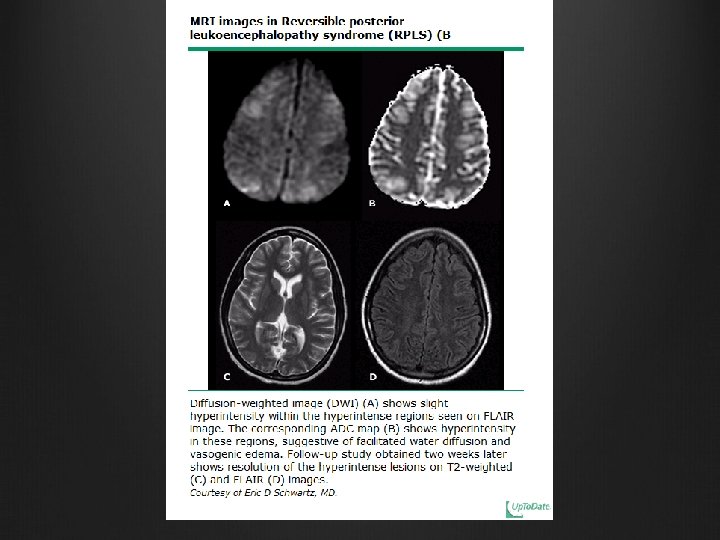

Neurological imaging MRI Much more effective than CT T 2 hyperintense signals at parieto-occipital and temporal lobes, occasional involvement of basal ganglia and/or brainstem ‘New’ MRI techniques for better characterization / differentiating from other causes E. g. diffusion weighted imaging and apparent diffusion coefficient mapping (ADC) Neurological complications of pre-eclampsia GG. Zeeman Seminars in perinatology 2009; 33: 166 -172

Neurological 2 theories trying to explain cerebral abnormalities in preeclampsia/ eclampsia with endothelial dysfunction having a central role 1. Vasospasm (cerebral overregulation in response to raised CPP/ hypertension with ischaemia and cytotoxic edema) 2. Hyperperfusion with breakdown of blood brain barrier with leakage of plasma/RBC with vasogenic edema (autoregulatory capacity of cerebral circulation exceeded with regions of vasoconstriction and forced vasodilatation) The latter one is more favoured and known as PRES (Posterior Reversible Leucoencephalopathy Syndrome) Neurological complications of pre-eclampsia GG. Zeeman Seminars in perinatology 2009; 33: 166 -172